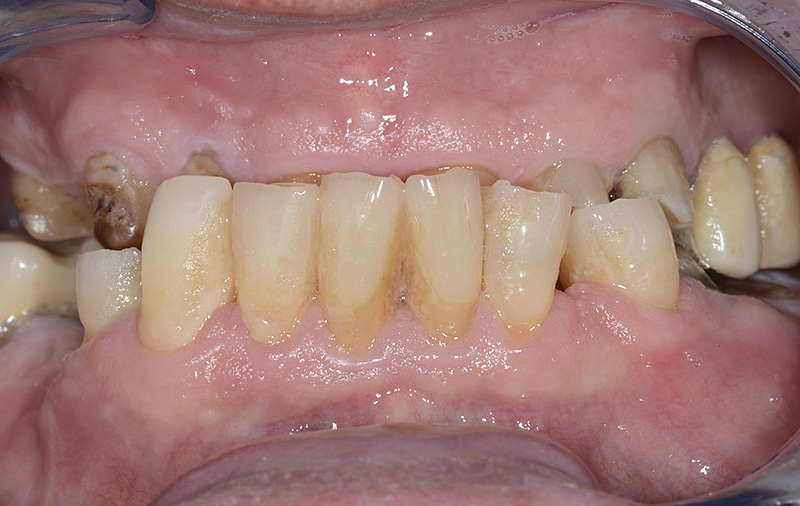

PREMESSA: in seguito all’estrazione dell’incisivo laterale superiore di destra, resasi necessaria per cause batteriche, si decide di affrontare il caso con il posizionamento di un impianto in sostituzione dell’elemento mancante dopo guarigione del sito infetto. Con tecniche rigenerative sia dei tessuti ossei mancanti a causa dell’infezione pregressa, sia dei tessuti gengivali che appaiono inizialmente troppo spostati in alto, si ripristina una corretta morfologia delle parabole (contorni) gengivali e delle papille interdentali (triangoli di gengiva tra due denti vicini).